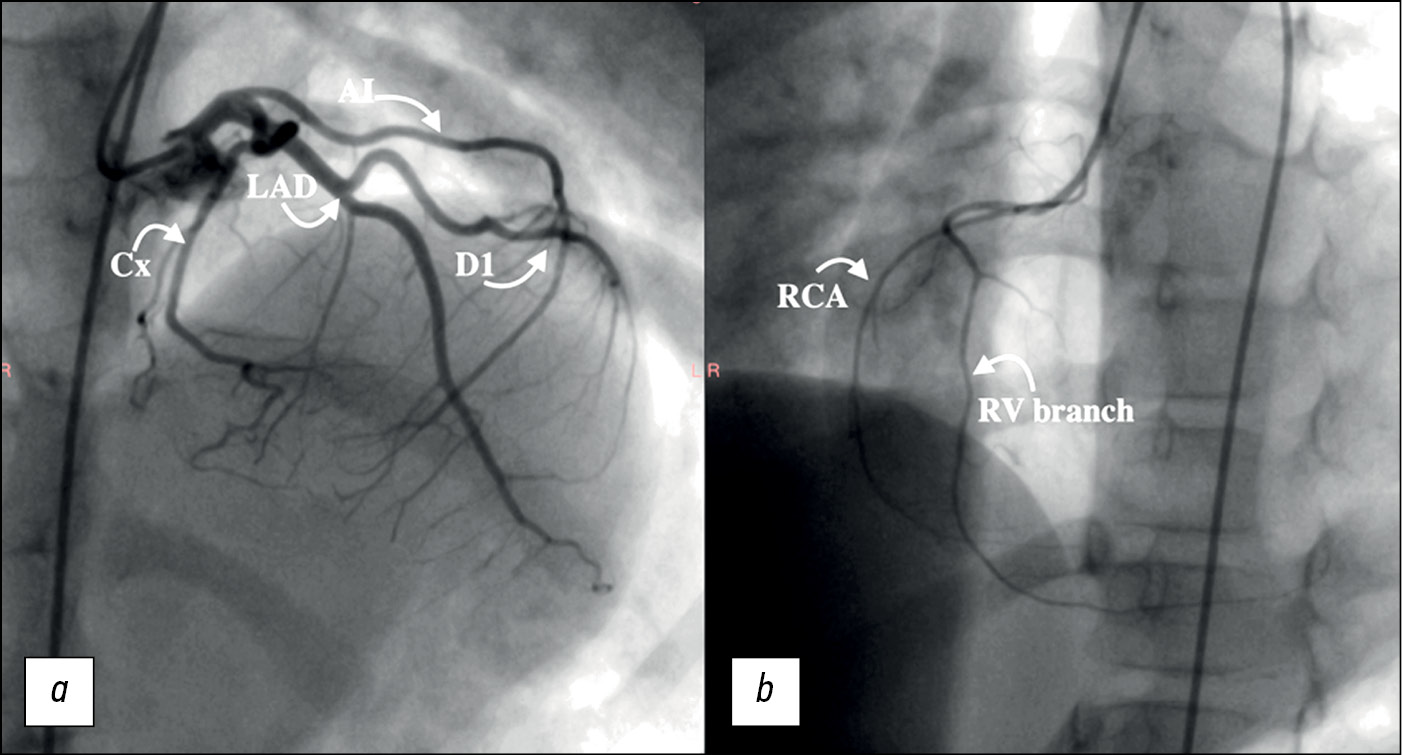

A cardiac magnetic resonance imaging (CMR) with contrast enhancement (Gadobutrol 2.0 mL) was performed to exclude congenital heart diseases. The systolic function of both ventricles was reduced (LV EF [41%] and RV EF [45%]). The total LV mass of the myocardium was 54.6 g, with noncompacted myocardium accounting for 14.4 g or 26.3% of the total. CMR revealed signs of myocardial scarring and aneurysmatic ballooning of the basal anterior and lateral-basal walls of the left ventricle, noncompact myocardium (with an NC-to-C ratio = 2.6:1), and left ventricular dilatation. Accumulation of contrast media (one, five, and six segments) in delayed scans was observed (Figure 2a–e).

Fig. 2. Magnetic resonance imaging of the heart in a 6-year-old patient with myocardial non-compaction and left ventricular aneurysm. The scanning was carried out on a 1.5-T magnetic resonance imaging scanner (MAGNETOM Avanto, Siemens Healthcare, Germany) with breath holding: a - on a two-chamber image along the short axis before the introduction of a contrast agent, a well-defined protrusion of the lateral wall of the left ventricle (asterisk) and local thinning of the myocardium (arrows). Echo time (Time of echo) - 1.5 ms, repetition time (Repetition time) - 42 ms; b — on a four-chamber image along the long axis before the introduction of a contrast agent, an aneurysm (asterisk) in the basal part of the lateral wall of the left ventricle and non-compact myocardium are determined (the ratio of non-compact and compact layers is 2.6: 1). Echo time - 1.5 ms, repetition time - 42 ms; c - on a four-chamber long-axis image after contrast, there is late gadolinium enhancement (arrows) in the basal region of the anterolateral wall of the left ventricle, where the aneurysm is located (asterisk). Echo time - 1.5 ms, repetition time - 700 ms; d - on a two-chamber short-axis image after contrast, the accumulation of contrast agent in the first, fifth and sixth segments is determined. Echo time - 1.5 ms, repetition time - 2000 ms; e - Two-chamber long-axis image shows late gadolinium enhancement in the basal anterior wall of the left ventricle. Echo time is 1.4 ms, repetition time is 700 ms.